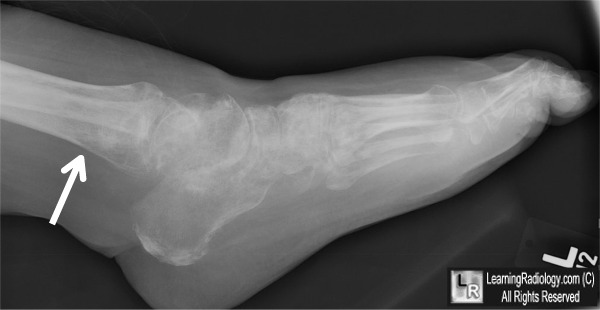

Một yếu tố ảnh hưởng đến chẩn đoán sớm tình trạng này là các dấu hiệu vận mạch trên lâm sàng không liên tục, và sự thiếu vắng dấu hiệu vận mạch tại một lần khám không nhất thiết loại trừ sự hiện diện của nó. Các dấu hiệu cũng có thể thay đổi về mức độ trầm trọng theo thời gian. Dị cảm đau là một dấu hiệu lâm sàng quan trọng, cảnh báo người bác sĩ khám bệnh khả năng của CRPS. Có nhiều tình trạng bệnh biểu hiện theo một cách tương tự và cần xem xét các chẩn đoán phân biệt với tất cả các bệnh nhân (Bảng 2). Một số xét nghiệm có thể trợ giúp chẩn đoán lâm sàng như X quang, có thể cho thấy bằng chứng thiếu xương cục bộ. Ghi nhiệt đồ và xạ hình xương ba pha có thể hiển thị những thay đổi cụ thể và MRI cũng có thể giúp chẩn đoán bằng cách loại trừ các bệnh lý khác như gãy xương do vận động lập lại (stress fracture).

- Ảnh do người dịch bổ sung